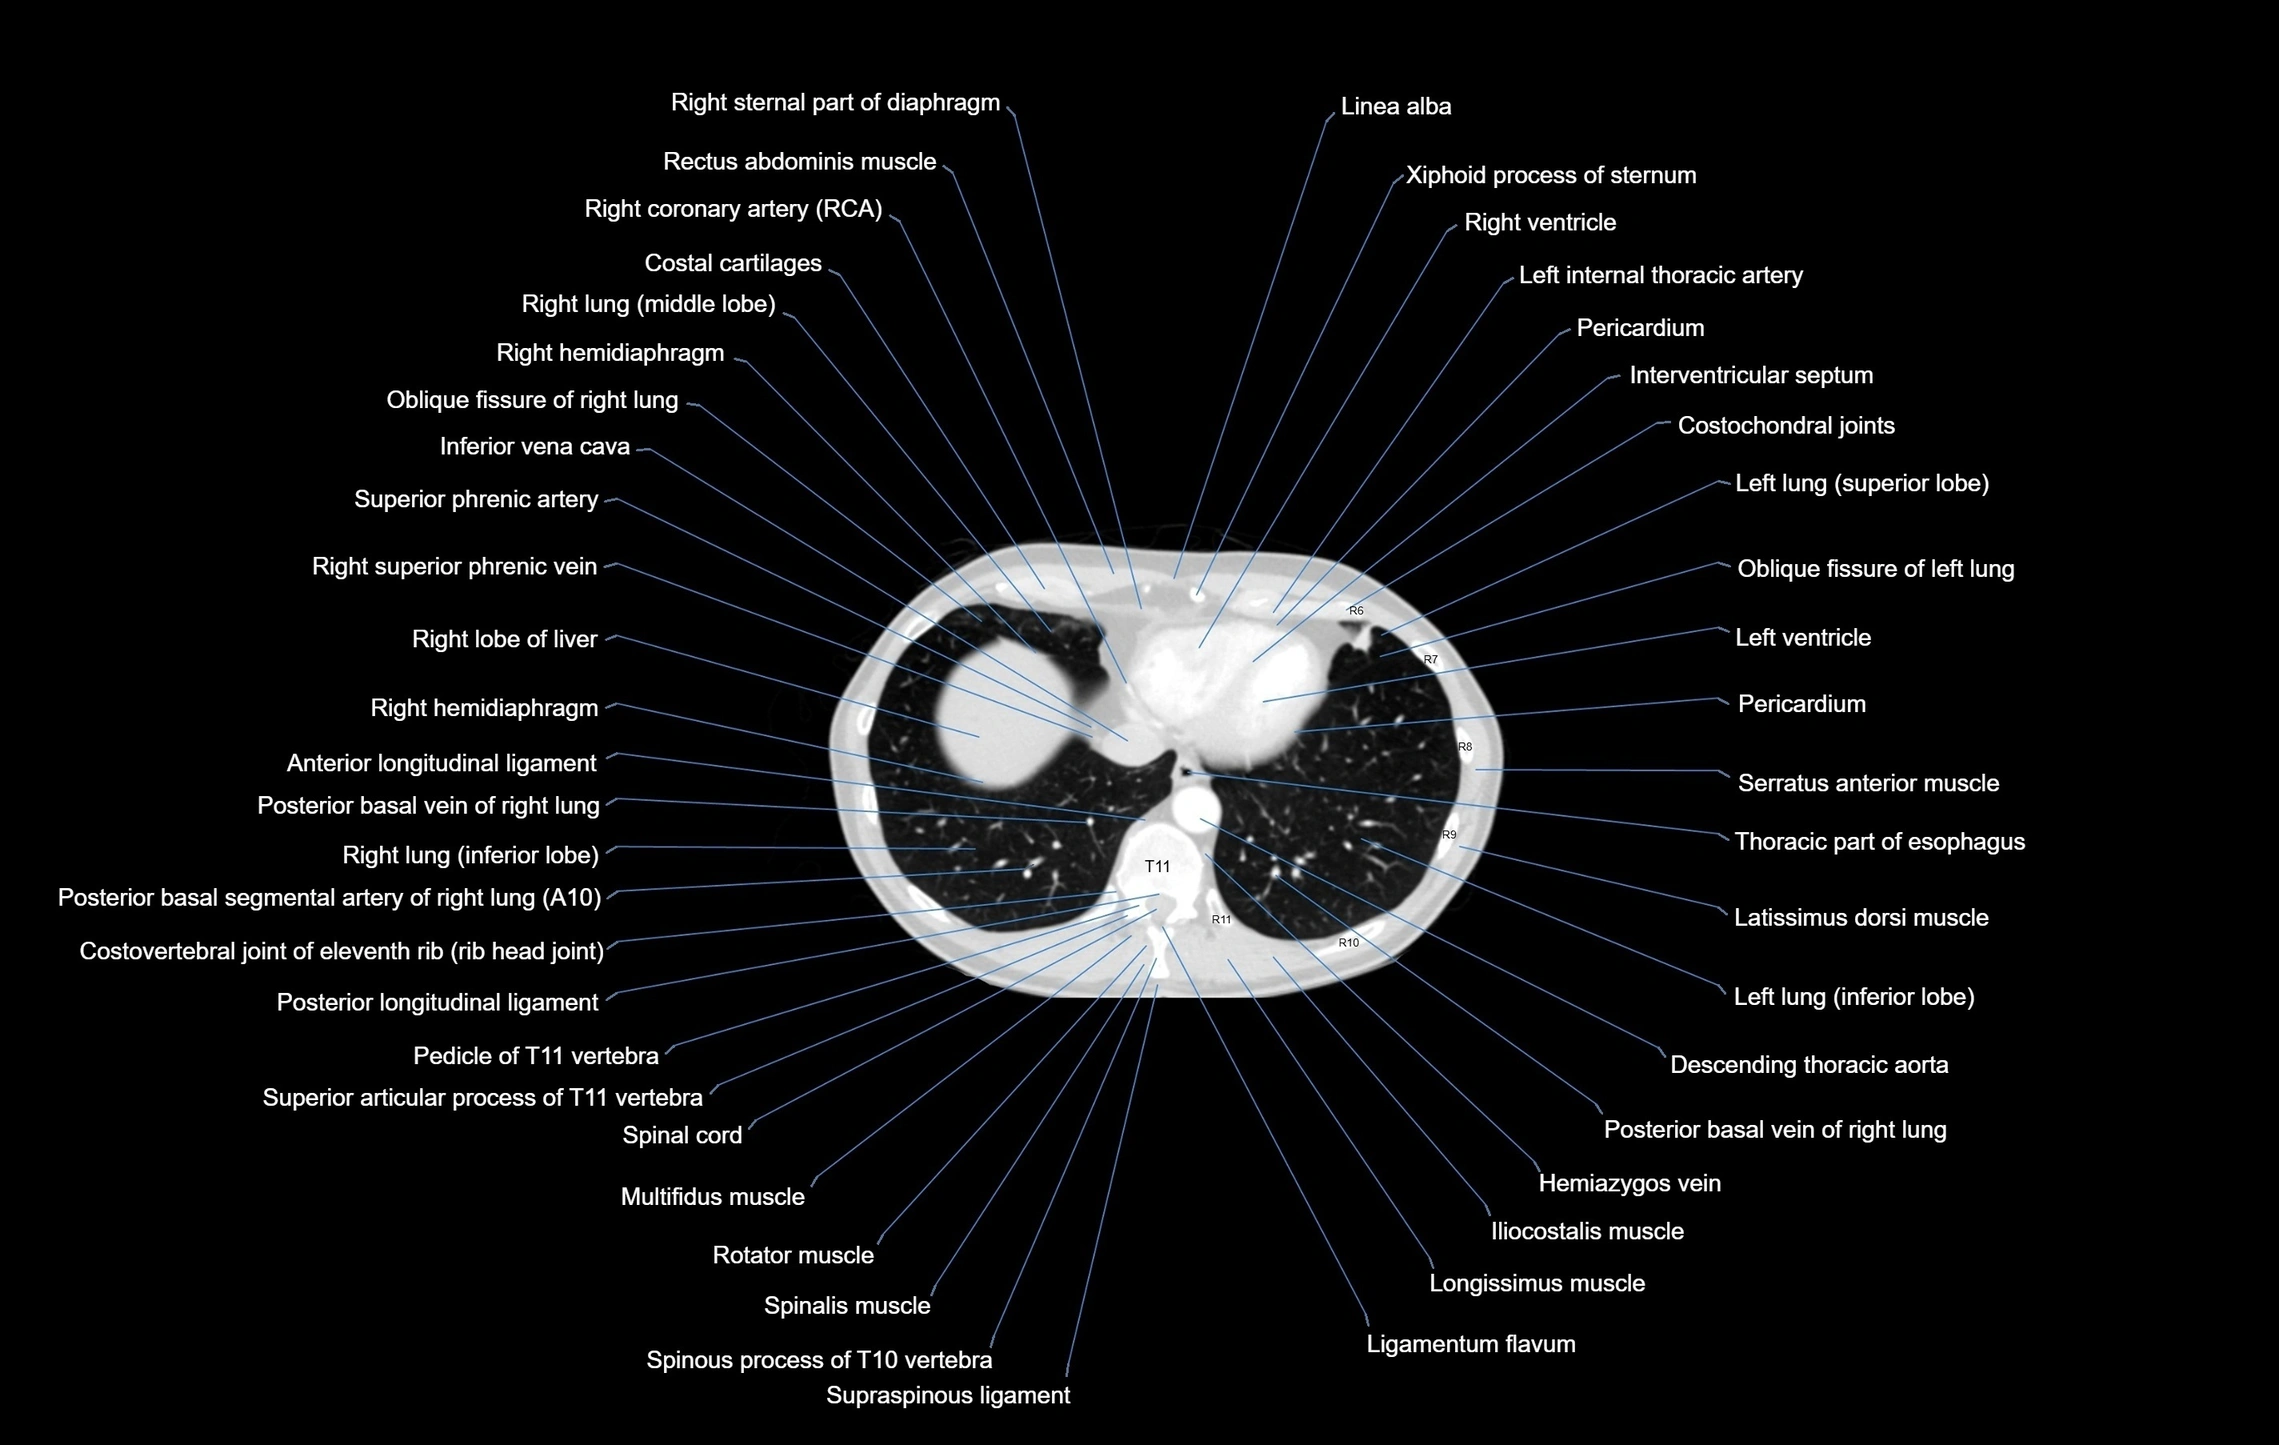

- Right ventricle

- Left ventricle

- Right atrium

- Interventricular Septum

- Pericardium

- Pericardial cavity

- Inferior vena cava

- Right hemidiaphragm

- Right lobe of liver

- Hemiazygos vein

- Descending thoracic aorta

- Oblique fissure of right lung

- Oblique fissure of left lung

- Multifidus muscles

- Rotatores muscle

- Posterior longitudinal ligament

- Ligamenta flava (Ligamentum flavum)

- Posterior basal vein of right lung